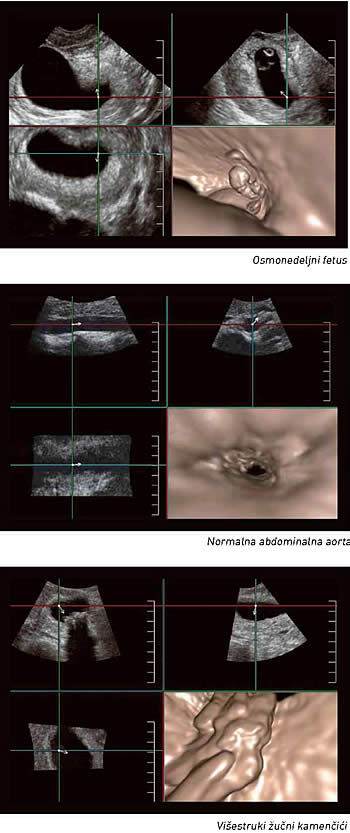

Virtuelna ultrazvučna endoskopija

Jedna od novih mogućnosti ultrazvučne tehnologija je FlyThru modalitet, koji omogućava jedinstvene adaptacije 4D imidžinga i daje endoskopsku sliku, ali bez interventne, invazivne procedure

Da će ultrazvuk nesumnjivo očuvati, ali i proširiti svoje suvereno mesto u dijagnostici uopšte, dokaz je jedan novi ultrazvučni sistem, koji predstavlja gospodin Andreja Gvozdenović, inženjer i stručnjak za medicinsku opremu u beogradskom “Beolaser”-u. Reč je sistemu komercijalno nazvanom Aplio 500 , koji je razvila kompanija “Tošiba”, a koji karakteriše niz naprednih mogućnosti vizualizacije. Jedna od tih novih mogućnosti je i tehnologija koju su njeni tvorci nazvali FlyThru , i koja je prva te vrste u ultrazvučnim dijagnostičkim sistemima uopšte. Baš kao što joj ime kaže, ona omogućava dijagnostičaru da 4D ultrazvučnom slikom virtuelno “leti kroz” unutrašnjost telesnih šupljina i krvnih sudova.

Reč je sasvim novoj perspektivi posmatranja telesnih struktura i slici koja je drugačija od svega poznatog u dosadašnjem ultrazvučnom imidžingu. FlyThru slika, naime, virtuelno putuje kroz telesnu šupljinu slično kao kod CT, odnosno slična je skenerskom prikazu. Gospodin Gvozdenović objašnjava da tipičan 4D imidžing koristi tzv. paralelnu projekciju posmatranog objekta, što onemogućava sagledavanje njegove “dubine” ili posmatranje prostora okolo tog objekta. FlyThru međutim, koristi perspektivnu projekciju, pa je dobijena slika identična kao u endoskopskim procedurama. Budući da su klasične endoskopske procedure invazivne, za pacijenta krajnje komforan ultrazvučni pregled, koji pri tom daje endoskopsku sliku, od ogromnog je značaja.

Osim što će u dijagnostici moći da zameni ili dopuni mnoge endoskopske procedure, FlyThru tehnologija obezbeđuje sliku izuzetne oštrine i jasnoće, te njene mogućnosti zapravo tek počinju da se istražuju u praksi. Ono što se sa sigurnošću sada može reći jeste da će FlyThru biti od ogromnog značaja u svim granama medicine. U ginekologiji, na primer, jedna od uzbudljivih mogućnosti je virtuelna histeroskopija. Ultrazvučni režim rada omogućiće da se polipi, miomi, srasline u materici ili bilo šta drugo unutar materične šupljine posmatra na sasvim nov način. Dva jedinstvena načina za korišćenje FlyThru u virtuelnoj histeroskopiji uključuju identifikovanje polipa i manipulisanje slikom tako da se polipi mogu videti i otpozadi, kao i procenjivanje stanja jajovoda, što je tradicionalnom histeroskopijom teško izvodljivo.

Naprednija dijagnostika

FlyThru omogućava da se vide i relativno male, fluidom ispunjene strukture od svega nekoliko milimetara, kao što su, na primer, prošireni kanali u dojci, što bi pomoglo u dijagnostikovanju intraduktalnih papiloma. U perinatologiji, u praćenju rane trudnoće, mogle bi se dijagnostikovati fetalne anomalije kao što su rascepljena (“zečja”) usna i druge anomalije lica. Imidžing neonatalne glave ovom novom metodom takođe je potpuno jedinstven način pregleda hidrocefalusa kod novorođenčadi.

Gastrointestinalni trakt takođe je polje gde bi se nova tehnologija mogla pokazati suverenom. Sposobna je, naime, da vizualizuje pankreasni kanal, žučnu kesu ili creva. Hidronefroze, kamen, opstrukcije, karcinomi tranzicionih ćelija ili čak lezije bešike vrlo kvalitetno se mogu ocenjivati putem FlyThru . Kad je reč o snimanju debelog creva , FlyThru daje slike veoma slične virtuelnoj kolonoskopiji (skenerskom pregledu debelog creva).

Venski sistem se, takođe, veoma jednostavno i kvalitetno može pregledati uz pomoć FlyThru . Mogu se uočiti venske tromboze, stenoze hepatičnih vena, ugrušci u perifernim venama. Kad je reč o aorti, tehnologija je jedinstvena po tome što može dati sliku sličnu intravaskularnom ultrazvuku, ali bez izvođenja interventne procedure.